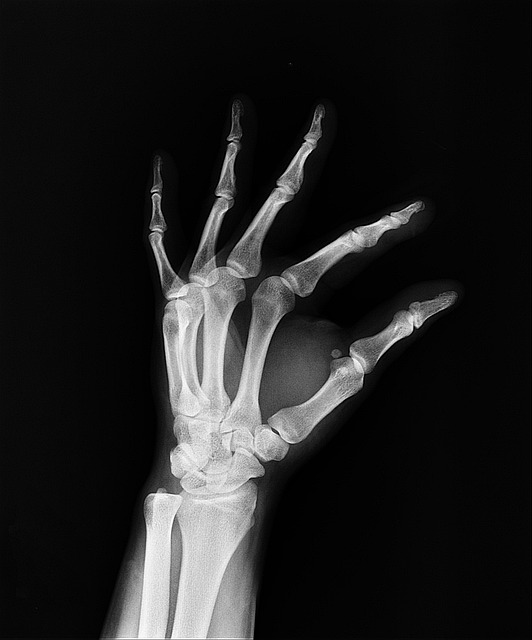

골다공증의 증상, 골다공증은 50세를 전후한 폐경기와 관련된 제1형 폐경기성 골다공증과 65세 이후에 발생되는 제2형 노인성 골다공증으로 구분한다. 제1형 골다공즈은 에스트로겐으로 치료가 가능하다. 발생 확률은 나이가 많고 여성을 제외하고도 근육과 지방질이 없는 사람 ,칼슘과 운동부족인 사람에게 발생률이 높다. 골절이 일어날 때까지는 별 자각증세가 나타나지 않는다. 또 골절이 되더라도 증상이 없는 경우가 대부분이며 약간의 경우 요통이 나타나기도 한다. 골다공증이 생기면 팔의 상박부 골절, 고관절 골절, 척추뼈의 압박골절이 잘 생긴다. 허리를 구부리거나 주저앉는 등 사소한 충격으로도 골절될 수 있다.